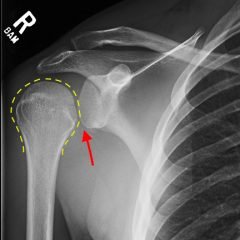

Radiographs of the knee showed multiple radio-dense lines paralleling the articular surface (see red arrows) consistent with calcium pyrophosphate crystal deposition within the joint often seen in calcium pyrophosphate disease (CPPD) also known as pseudogout.

Patients commonly present to the emergency department with non-traumatic joint pain. Arthrocentesis is an important diagnostic tool to evaluate for septic arthritis, gout, or pseudogout. Arthrocentesis can demonstrate crystals or abnormal cell count, gram stain, and culture.[1] In the evaluation of joint pain, plain films are usually obtained to evaluate for fracture, dislocation, effusion, or secondary signs of infection. In this case the classic x-ray supported the diagnosis of CPPD.2 The patient was found to have positively birefringent rhomboid shaped crystals consistent with pseudogout on arthrocentesis. Gram stain and culture were both negative. The patient was discharged with NSAIDs and had significant improvement in symptoms upon follow up with primary care physician in 3 days.